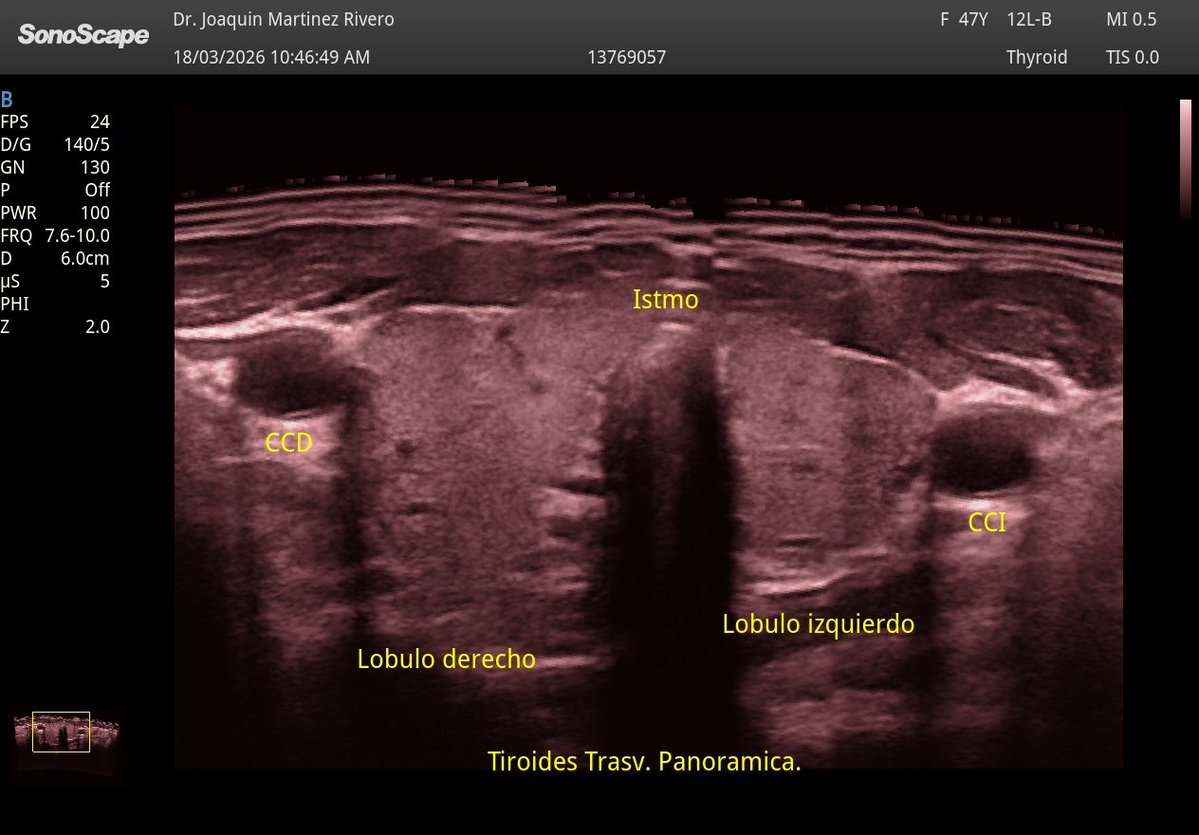

Una de las cosas que más he notado con la mejora de nuestro equipo es la calidad del doppler, ¡qué diferencia!